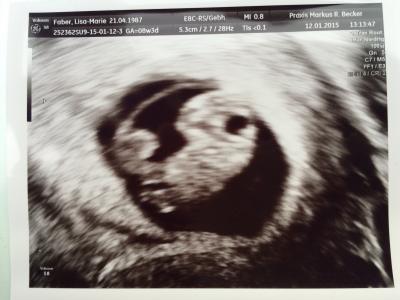

Heute endlich der Termin beim Frauenarzt gewesen! Der neue Arzt hat sich viel Zeit genommen und mir meine Fragen beantwortet! Baby zappelt ganz doll und herz schlÀgt ganz fröhlich vor sich hin... 1,8 cm 8+3 Woche wie ich mir auch selbst ausgerecht hab! ET ist der 21.8

Bild zu Endlich... 😊 - Forum fĂŒr August - Mamis

Klingt super :) Hat er was zu dem buppel in der Nabelschnur gesagt? Aber wie krass man die schon sieht oO

Ich glaub das sind die FĂŒĂŸe! Aber er hat gesagt es ist alles in Ordnung! Alles wie es sein soll! Aber das es sich schon bewegt find ich krass! Kann mich nicht mehr erinnern das es bei meiner ersten SS auch so war!